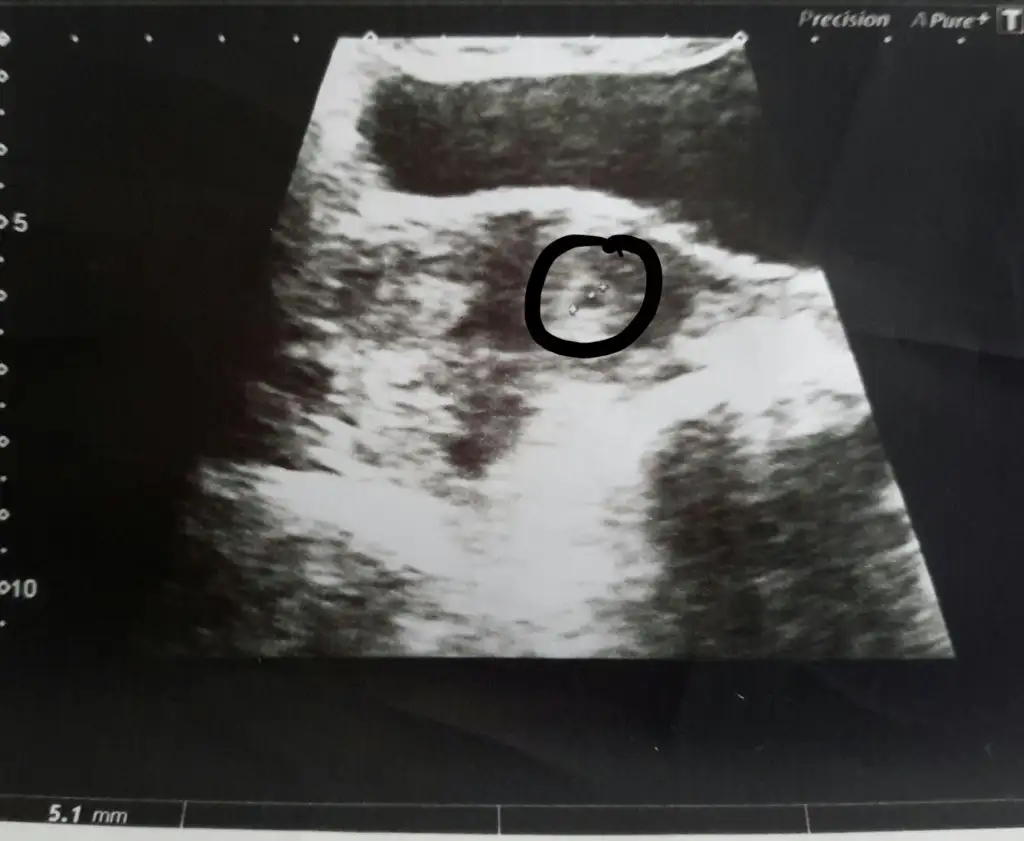

arkdaslar merhaba, bu ultrasonum 4 hafta 6 gunlukken yapildi. goruntusu benzer olan var mi, ve benim dikkatimi cekti alttaki kesnin ustunde ona bitisik

minik bir kese daha mi var yoksa yolk kesesi mi o bilemedim. doktorda bisey demedi, haftaya gel dedi, carsamba gunu gidecegim.

arkdaslar merhaba, bu ultrasonum 4 hafta 6 gunlukken yapildi. goruntusu benzer olan var mi, ve benim dikkatimi cekti alttaki kesnin ustunde ona bitisik Eki Görüntüle 1581189 minik bir kese daha mi var yoksa yolk kesesi mi o bilemedim. doktorda bisey demedi, haftaya gel dedi, carsamba gunu gidecegim.

bu sekilde gozukmesi normal cizdigin yer dogru cnm 4+6 gunluk kese henuz yolk sac olus maz